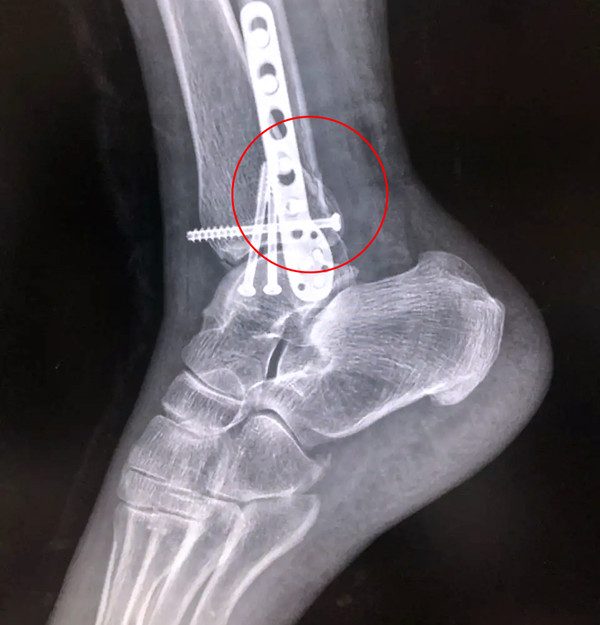

【醫(yī)療科普】Pilon骨折

有一種特殊類型的踝關(guān)節(jié)骨折,可能在X影像平片上就不能顯示出來,它就是脛骨的關(guān)節(jié)面往里塌陷,我們又稱之為叫“Pilon骨折”。當(dāng)它往里塌陷后,我們?cè)赬影像平片上可能看不出來它是否塌陷,但是我們?cè)贑T上可以360°看到踝關(guān)節(jié)的影像,這樣就可以看出患者是否存在踝關(guān)節(jié)塌陷的骨折。同樣道理,我們?cè)谧鯬ilon骨折手術(shù)的時(shí)候,普通二維的X影像并不能判斷我們手術(shù)復(fù)位情況的好壞,這個(gè)時(shí)候如果醫(yī)生手上有能夠照三維影像的工具,那么對(duì)于醫(yī)生的準(zhǔn)確手術(shù)是非常有好處的。